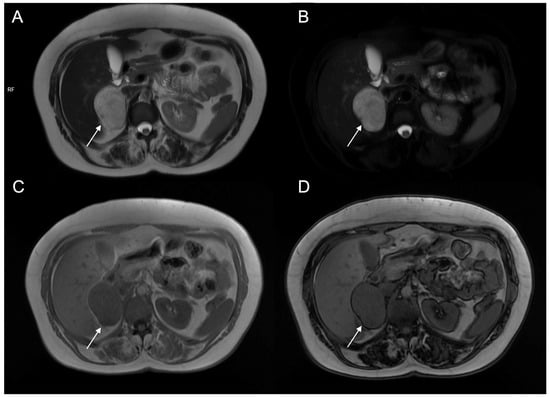

Figure 11.

A 48-year-old female with hypertension and tachycardia. MRI revealed a solid mass (arrow) of the right adrenal gland measuring 55 × 42 mm. The mass was uniformly hyperintense on T2-weighted images (A) and on T2-weighted sequences with fat suppression (B), hypointense on T1-weighted in-phase image (C) without signal loss in the opposition-phase image (D). The clinical and radiological suspicion for pheochromocytoma was confirmed by histology.